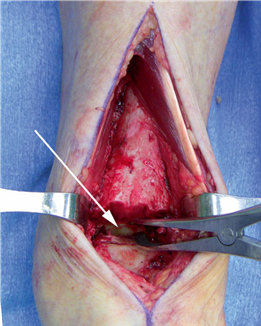

The Lapidus Arthrodesis (First TMT Fusion)

For severe deformities or hypermobility, the Lapidus procedure provides robust stabilization of the medial column. A dorsal or medial incision is utilized over the first TMT joint. The extensor hallucis longus (EHL) is retracted dorsally, and the tibialis anterior tendon is identified and protected at its insertion on the medial cuneiform and first metatarsal base. The TMT joint capsule is incised, and the joint is thoroughly debrided of all articular cartilage using a combination of osteotomes, curettes, and a high-speed burr.

To achieve multiplanar correction, the surgeon must address the sagittal, coronal, and transverse planes. The first metatarsal is plantarflexed to restore the longitudinal arch, rotated out of pronation to realign the sesamoids, and translated laterally to close the IMA. Subchondral drilling or feathering is performed to optimize the biological environment for fusion. Fixation is traditionally achieved with two or three crossed solid or cannulated screws (typically 3.5mm or 4.0mm). Recently, plantar or medial locking plates have gained immense popularity due to their superior biomechanical construct, allowing for earlier weight-bearing. Bone graft or orthobiologics may be packed into the arthrodesis site to stimulate osteogenesis.